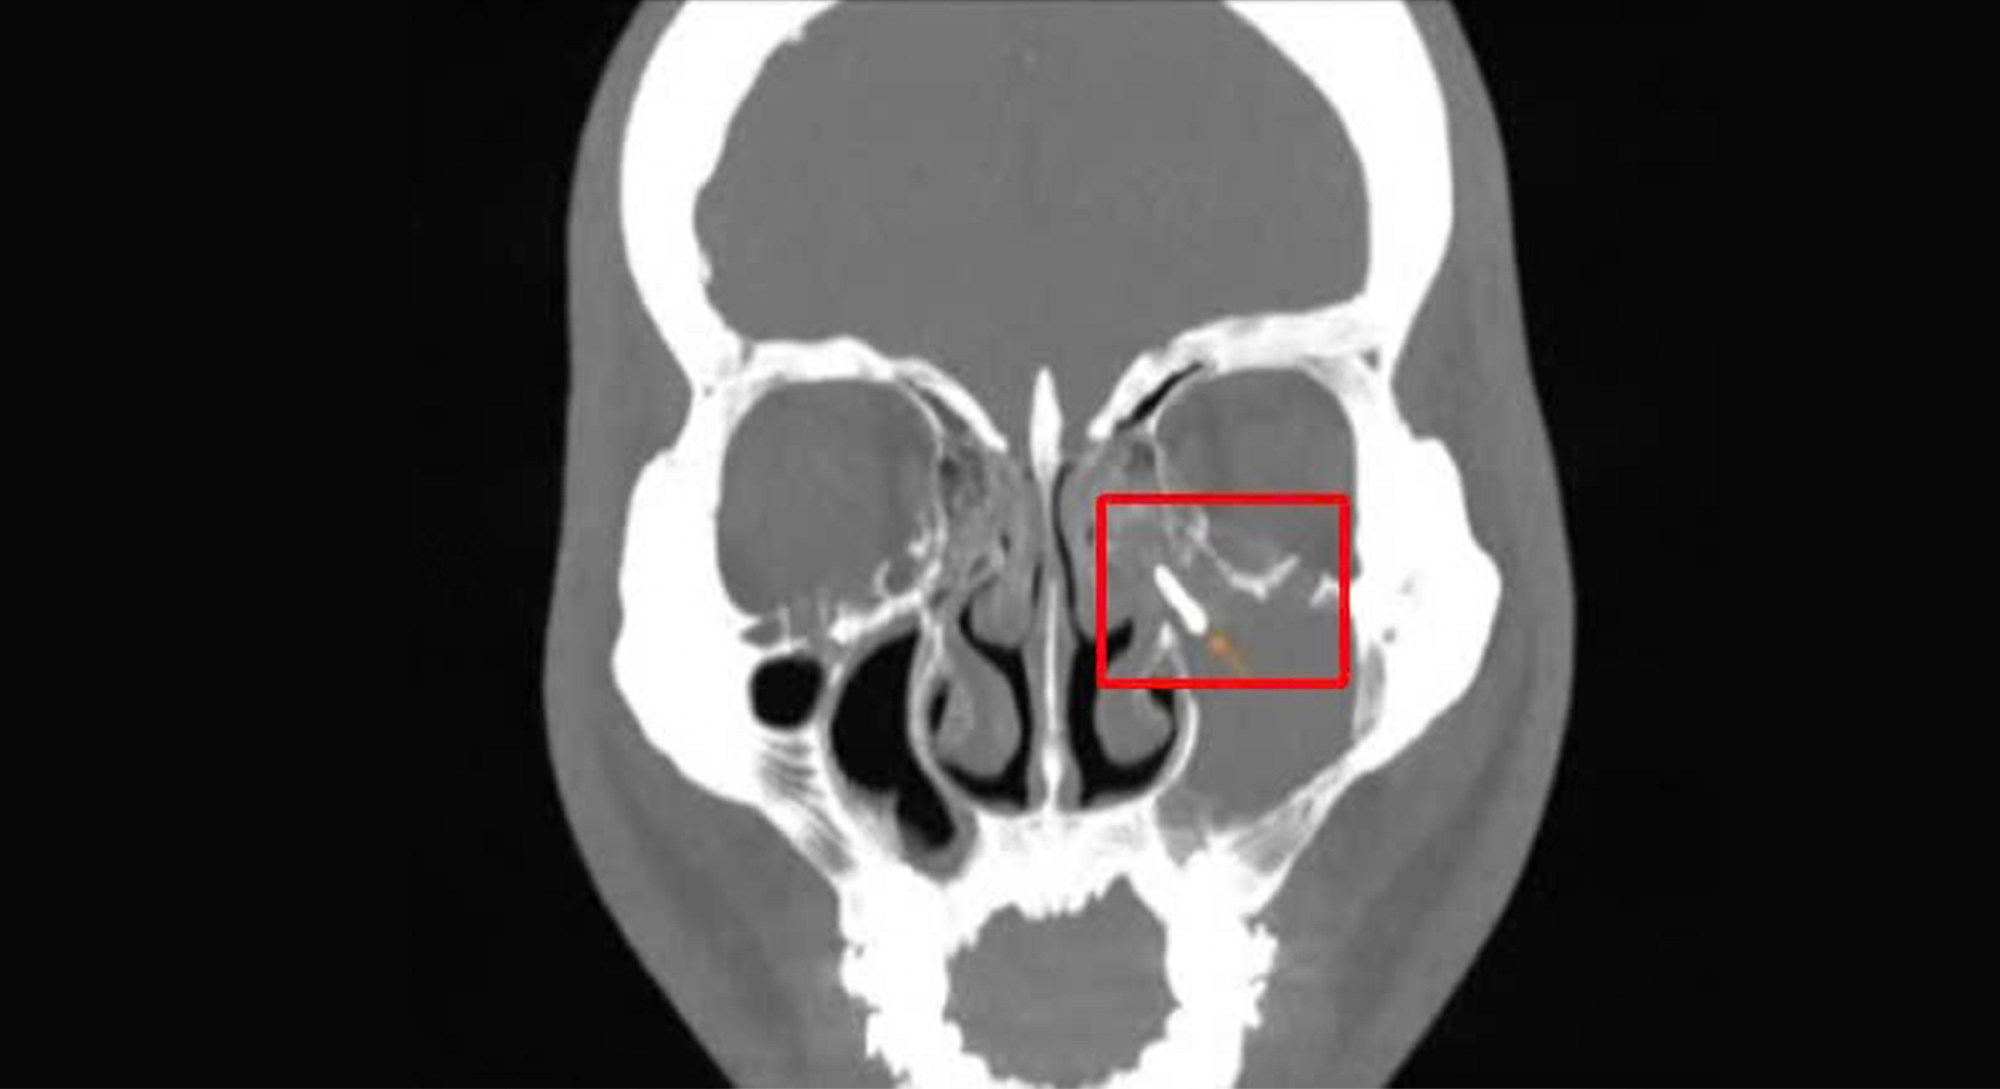

The CT scan confirmed a foreign metallic object within Mr. Phu's left maxillary sinus. It also showed the sinus cavity filled with inflammatory lesions, sclerotic sinus walls, and a blocked sinus ostium. Additionally, the roots of his 15th, 16th, and 17th teeth protruded close to the maxillary sinus, with slightly thickened sinus mucosa. Based on these findings, Dr. Duy diagnosed purulent maxillary sinusitis caused by a foreign body and recommended endoscopic sinus surgery to remove it and prevent further infection.

CT scan revealing the foreign body in Mr. Phu's left maxillary sinus. *Photo: Tam Anh General Hospital*